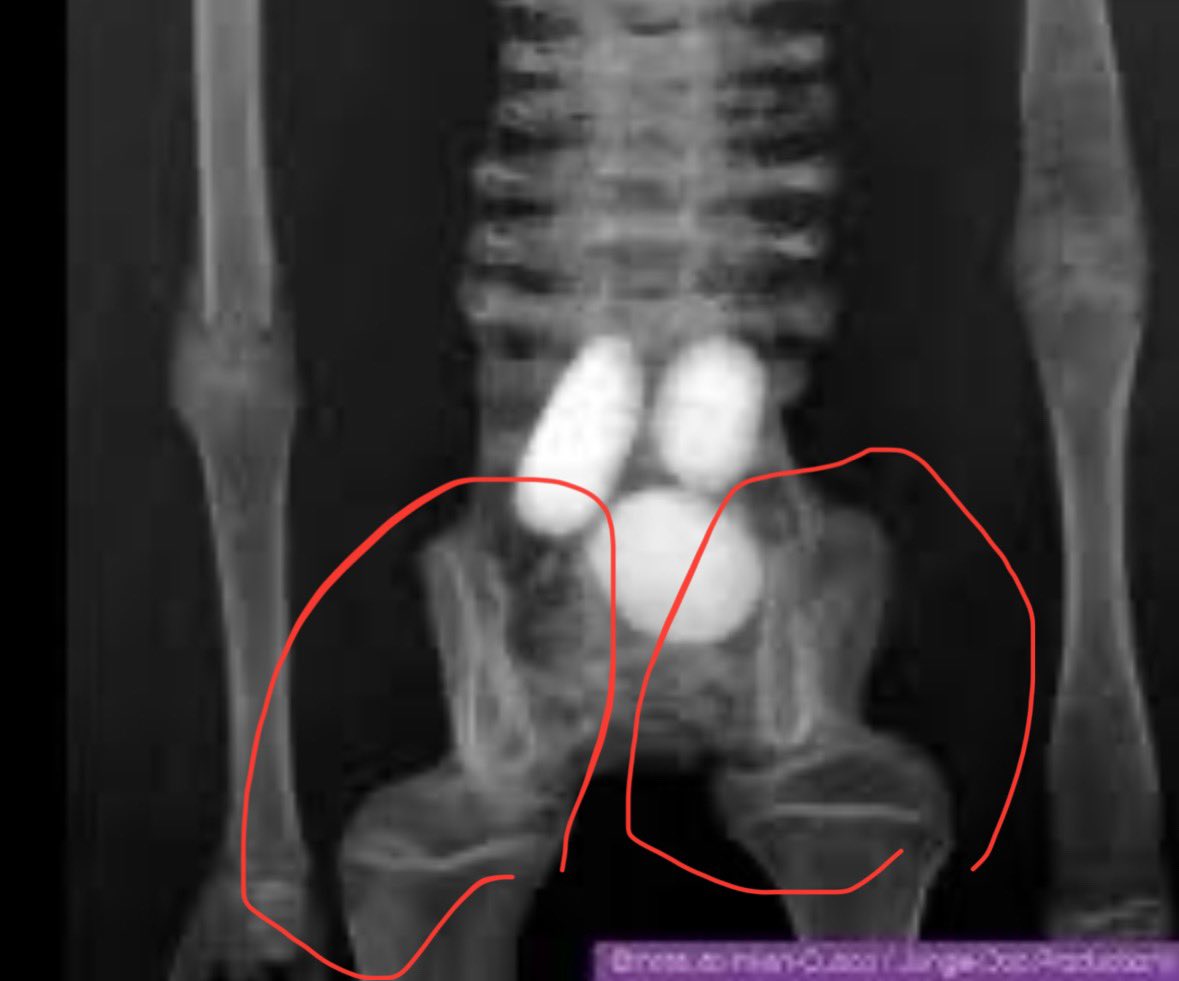

They’re taking real human mummies then removing two of the fingers and toes, and using those removed bones to extend the remaining digits. Then they use the white diatomaceous earth to cover their cut marks. In some cases you can see where they used metal to hold those modified

Notice how, unlike the other toes, the bones on the left are narrower towards the foot and wider towards the toes. If this were real you’d expect the right and left feet to exhibit similar anatomy. Yet more proof that these nazca mummies are a scam. How many red flags do

@JosephAPWilson1

EXPOSE the criminals. #NAZCAMUMMIES #ScamAlert Look at the terrible incompetent grisly human body part sculpture in the mutilated human mummy known as PALOMA. They inserted extra bones HAPHAZARDLY with the wrong orientation. They think you are STUPID. #JusticeForNazca

@TonyTrupp @GGSH099 @tridactyls In these image of Maria's hands you can see how they inserted extra bones to make the fingers longer - just as they did with the feet. But they were sloppier with the orientation of some of them!